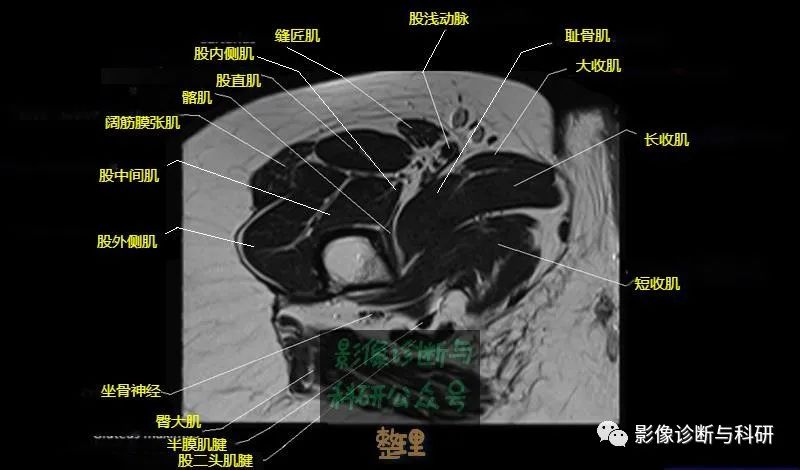

髋关节MR轴位详细标注

大腿肌配布于股骨周围,分前、后和内侧三群

前群

位于大腿前面,有缝匠肌和股四头肌。

作用:伸膝关节,股直肌带可屈髋关节。

内侧群

位于大腿内侧,共5块,其中股薄肌位于最内侧;另4块分三层,浅层靠外上方为为耻骨肌,下方为肌长收肌。长收肌深面是第二层的肌短收肌。第三层是强有力的大收肌。这一群肌均起自耻骨支和坐骨支,除股薄肌止于胫骨上端内侧外,其余各肌都抵止在股骨粗线。

作用:大腿内收。

后群

位于股骨后方,包括股二头肌、半腱肌和半膜肌。

作用:屈膝关节、伸髋关节。